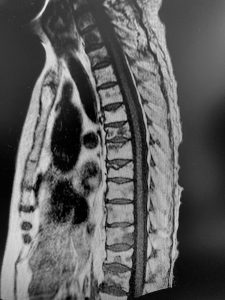

- Compresión de la médula espinal: Si el tumor afecta a la columna vertebral, puede comprimir la médula espinal, llevando a debilidad, entumecimiento o parálisis.

- Diagnóstico por imagen: Radiografías, resonancias magnéticas (RM), tomografías computarizadas (TC) y gammagrafías óseas ayudan a localizar y evaluar la extensión de las metástasis.